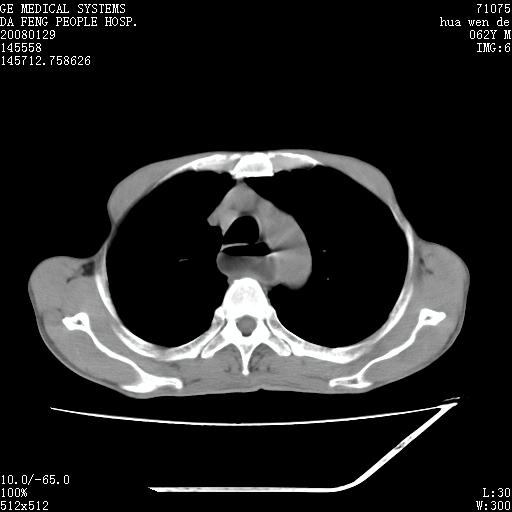

男性,67岁。作肺部检查时发现

考虑:胸腔胃并支气管瘘(并发吸入肺炎,肺脓肿形成)。

理由:1、右上肺内病灶,空洞形成,有液平。

2、肺内多处炎症。

3、前段肺内炎症,支气管引流通畅,与肿块无关系。

1.整个食管扩张,未见明显占位性病变,贲门区亦未见明显占位病变,考虑:贲门失驰缓症;

2.右上肺病变边缘可见毛刺,囊壁厚度不均匀,周围境界较清楚,未见炎性渗出性影,右上肺外带可见片状影,边缘不清,考虑:肺癌伴空洞形成、右上肺炎。

15楼主分析有道理,胸腔胃除外,那么考虑贲门失驰缓症并肺部化脓感染(吸入性)可能。

肺内病灶位于右肺中叶,食道扩张后导致咽部功能受影响,吸入气管可能是存在的。

可疑之处在于:左肺未见吸入性病灶存在。另右肺癌(右肺中央型并阻塞性肺炎)不能除外

食管全程扩张,壁均匀不厚,喷门失弛缓症

右上肺空洞可见液平,临近肺野磨玻璃密度,考虑1.结核2.脓肿